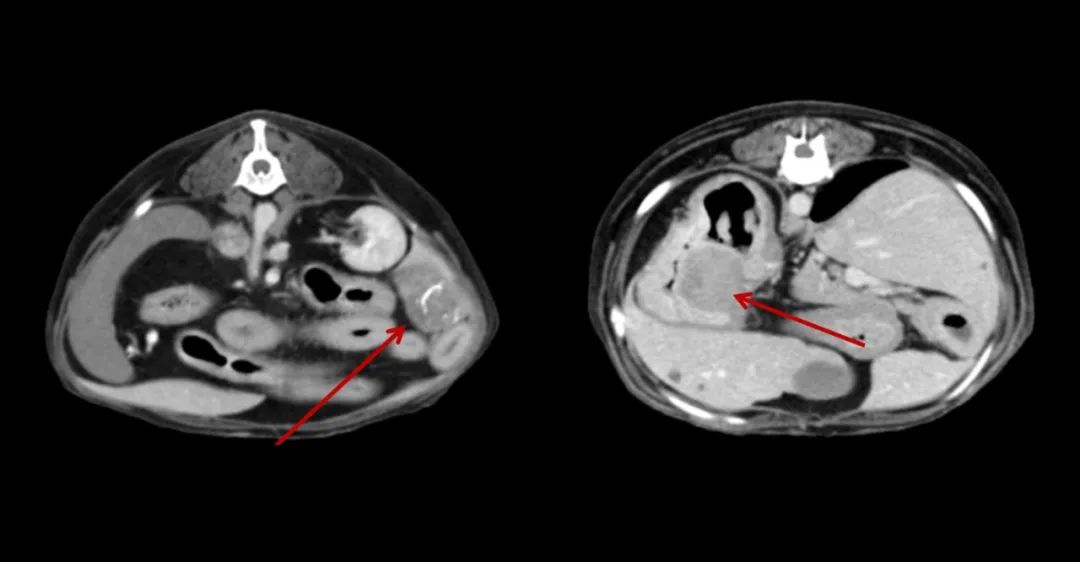

▲7歲,38kg的金毛狗近期總是嘔吐,CT全身平掃+增強,發(fā)現(xiàn)肝和胃占位性病變。

▲7歲成年犬,乳腺癌術(shù)后1年,發(fā)現(xiàn)肺部轉(zhuǎn)移。